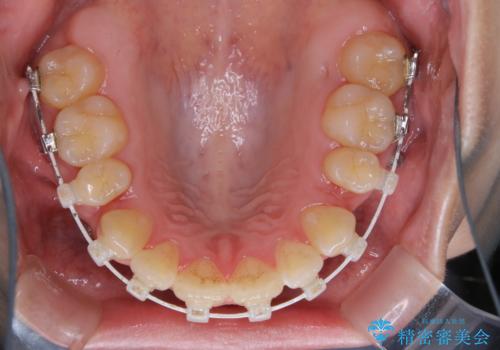

ワイヤー矯正中のクリーニング

- ワイヤー矯正中に、磨ききれないところがあるのと、口臭が気になるとのことでした。

そのためPMTC30分コースを行いました。

ワイヤー矯正中は、装置の周りに汚れが付きやすく虫歯や歯周病のリスクが高まります。そのため、ワイヤー調整の診察の際、一緒にクリーニングを行うことで、虫歯・歯周病・口臭予防になります。歯ブラシだけでは取り除くことが難しい細かい部分などに、専門的な機械や機材を使用して定期的なケアを行うことをおすすめしています。